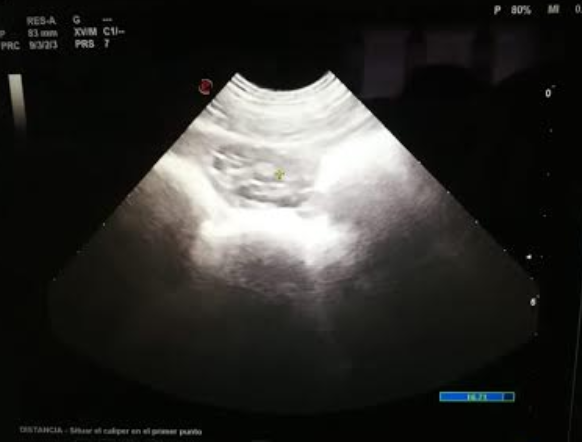

Figura 2. Imagen de la izquierda: medición de útero de 0,8cm. Derecha: ovario en anoestro, inactivo con folículos de menos de 4mm.